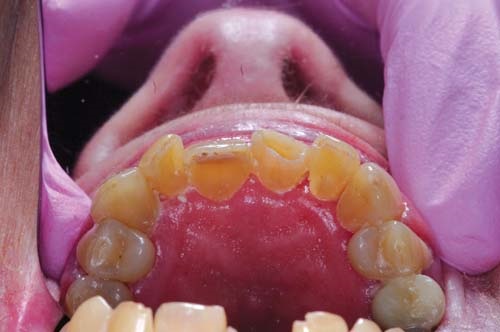

After removal of the caries (Fig. 3, p. 27) I fitted a generic strip crown and marked the junction to her facial enamel on the crown form (Fig. 4, p. 27). This allowed me to know exactly where to place the darker conventional composite as a facial veneer (Fig. 5). This veneer would not interfere with the benefits of the flowable bioactive composite for both the placement and the sustainability of the restoration.

Fig. 4: The junction to the facial enamel is marked on the crown form. The incisal edge of the crown form is perforated at both corners with an explorer tip to allow for venting of air. The perforation is made from the internal aspect outward, to avoid a negative flaw in the resulting veneer.